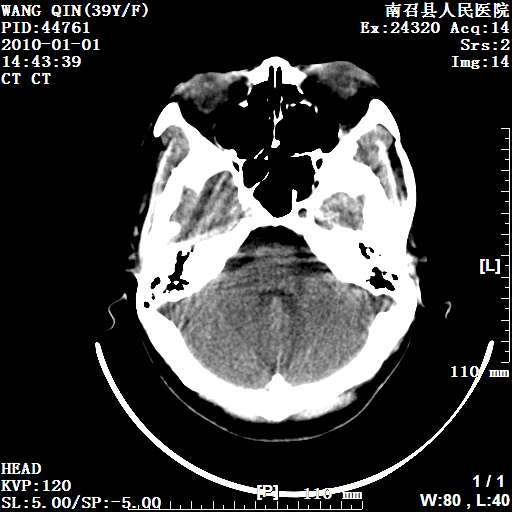

以下是引用随光逐影在2010-1-22 9:03:00的发言:[br]考虑左侧中颅窝(蝶骨翼区)脑膜瘤侵犯蝶骨翼并突入左侧眼眶。

以下是引用水过无痕在2010-1-22 14:55:00的发言:[br]一、定位:颅外占位;二、定性:恶性可能性大;三、组织来源:来源于左侧眼外直肌或其他部位;考虑为:横纹肌肉瘤>转移瘤>脑膜瘤.